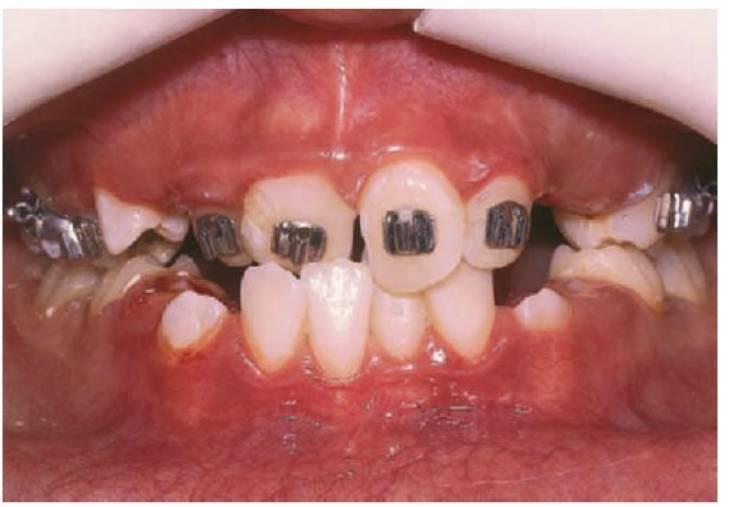

Las caries de gran tamaño que afectan a los primeros molares permanentes plantean un dilema difícil en la planificación del tratamiento, y la presentación temprana del paciente resulta esencial para obtener resultados favorables (figs. 11.8, 11.9). Las preguntas básicas sobre si se debe o no restaurar estos dientes son:

- ¿Cuál es el pronóstico a largo plazo para el diente?

- ¿Cuál es el estado de la pulpa?

- ¿Están totalmente formados los ápices radiculares?

- ¿Están presentes los terceros molares?